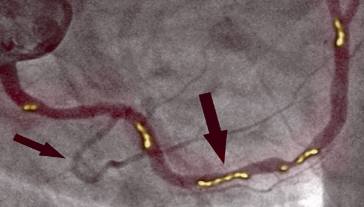

ПРЕДИ ТЕРАПИЯТА

На снимката вляво виждаме стесняване на дясната коронарна артерия при 66-годишен мъж, диагностицирана чрез инвазивна коронарна ангиография. Може да се види значителна стеноза в проксималния участък, причинена от калцифицирана атеросклеротична плака, която блокира притока на кръв.

СЛЕД ТЕРАПИЯ

На снимката вдясно виждаме почистената дясна коронарна артерия без следи калцифицирана атеросклеротична плака при същия пациент след 1 месец терапия. Няма смъртоносни холестеролни отлагания. Кръвта тече свободно, насищайки всички органи с кислород.